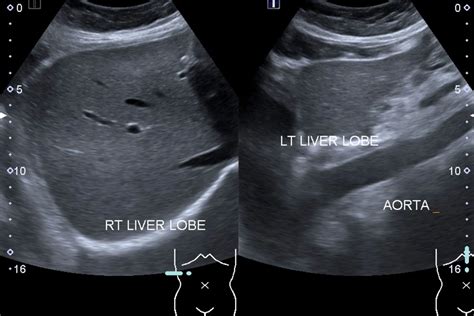

Interpreting the results of a liver ultrasound involves assessing the images for any abnormalities. A normal liver ultrasound will show:

• Size and Shape: The liver should be of normal size and shape, with smooth edges.

• Echogenicity: The liver tissue should have a uniform echogenicity, indicating a healthy structure.

• Blood Flow: Normal blood flow through the liver and its vessels.

• Absence of Abnormalities: No cysts, tumors, or other abnormalities should be present.

A liver ultrasound is a diagnostic imaging test that uses high-frequency sound waves to create detailed images of the liver. This procedure is commonly used to evaluate the liver’s size, shape, and internal structure. It can also detect abnormalities such as cysts, tumors, and fatty liver disease. The test is painless, non-invasive, and does not involve radiation, making it a safe option for patients of all ages.

• Scanning: The technician will move a transducer (a handheld device) over the abdomen, emitting sound waves and capturing the reflected echoes to create images.